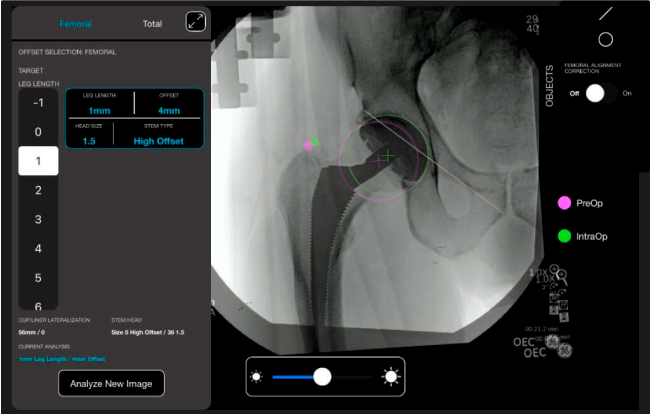

Planeación preoperatoria mediante la creación de plantillas digitales para reemplazo de cadera y análisis intraoperatorio

Favorece la restauración biomecánica del offset femoral.

Desplazamiento y offset para posicionamiento óptimo del componente (vástago) femoral.

Anotaciones digitales y herramientas de análisis de longitud de pierna.

Con tecnología ONETRIAL® que calcula automáticamente el cambio en la longitud de la pierna y el desplazamiento para todas las combinaciones de implantes en una tabla fácil de leer.